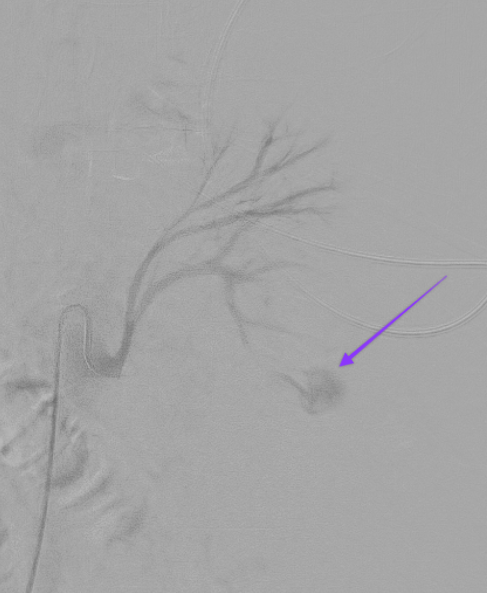

58 year old cirrhotic patient, underwent renal biopsy at outside facility. 1 day of progressive abdominal pain. CT with active bleeding from biopsied kidney.

#IRad quick to#embolize the vessel and#stopthebleed#MIIP#InnovationToHeal#Radiology#TwittIR#IRadRes pic.twitter.com/8GcA0rVLtE